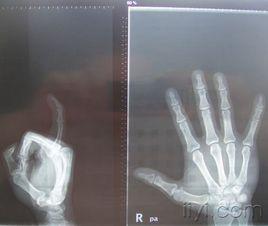

指間關節,又名指骨間關節interphalangeal joint,由上一節指骨滑車與下一節指骨底構成,為滑車關節,只能做屈伸運動。

手指間關節,由近節指骨滑車與遠節指骨基底部構成。分為近側和遠側指間關節。指間關節脫位較為常見,各手指的近側或遠側指間關節均可發生。脫位的方向多為遠節指骨...